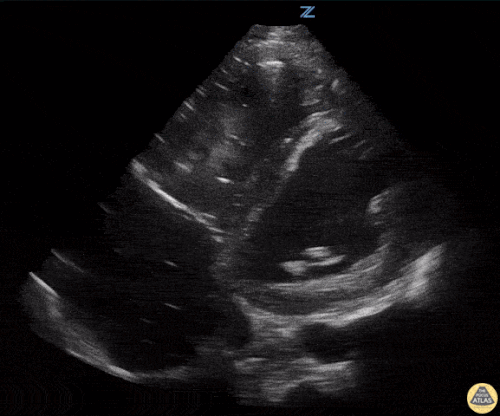

Apikal dört boşluk

Sağ ventrikül fonksiyonunun değerlendirilmesi

Sağ ventrikül, önceki bölümde anlatılan temel kardiyak pencereler kullanılarak değerlendirilebilir. Normalde sağ ventrikül düşük basınçlı bir odacıktır ve sol ventriküle kıyasla daha küçük görünür.

Sağ ventrikül disfonksiyonunda özellikle şu bulgulara bakılır:

Sağ ventrikül dilatasyonu

Septal bombeleşme (septal bowing)

Apikal dört boşluk görüntüsünde sağ ventrikül normalde sol ventrikülün yaklaşık üçte ikisi büyüklüğünde olmalıdır. Eğer iki ventrikül aynı boyutta görünüyorsa bu durum anormal kabul edilir ve dilatasyon düşündürür.

Bir diğer önemli bulgu McConnell belirtisidir. Bu bulgu, sağ ventrikül serbest duvarında hipokinezi bulunurken apeksin korunmuş olması şeklinde tanımlanır.

Önemli bir hata, sağ ventrikül disfonksiyon bulgularını otomatik olarak akut bir sürece (örneğin pulmoner emboli) bağlamaktır. Yukarıda belirtilen bulgular hem akut hem de kronik durumlarda görülebilir. Bu nedenle klinik bağlam ve hasta öyküsü önemlidir. Önceden yapılmış bir ekokardiyografi raporu, yatak başı değerlendirme ile karşılaştırma yapmak açısından çok yardımcı olabilir.

Apikal dört boşluk görüntüsü alınırken dikkatli olunmalıdır. Eğer görüntü aks dışı alınırsa sağ ventrikül kısalmış (foreshortened) görünebilir ve dilatasyon gözden kaçabilir. Bu hatadan kaçınmak için probu hafifçe döndürerek sağ kalbin en geniş göründüğü düzlemi yakalamak gerekir.